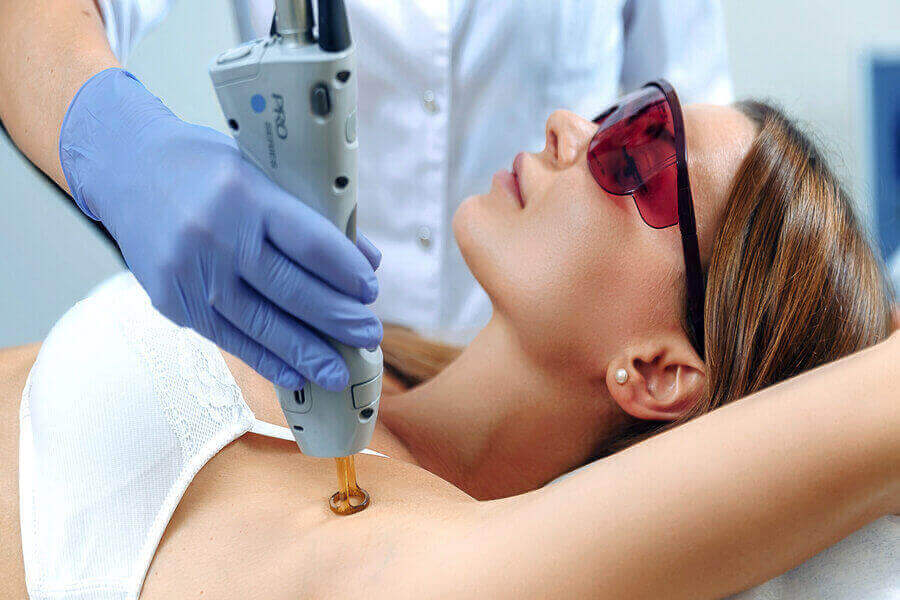

ՆԱԽԱԲԱՆ HIFU-ն ( High Intensity Focused Ultrasound ) բարձր ինտենսիվության կենտրոնացված ուլտրաձայն է մաշկի ձգման ( լիֆթինգի ) համար: Ամերիկայում մշակված HIFU սարքը առաջացնում է ուլտրաձայնային իմպուլսներ, որոնք ներթափանցում են դեմքի մակերեսային մկանային ապոնևրոտիկ համակարգ